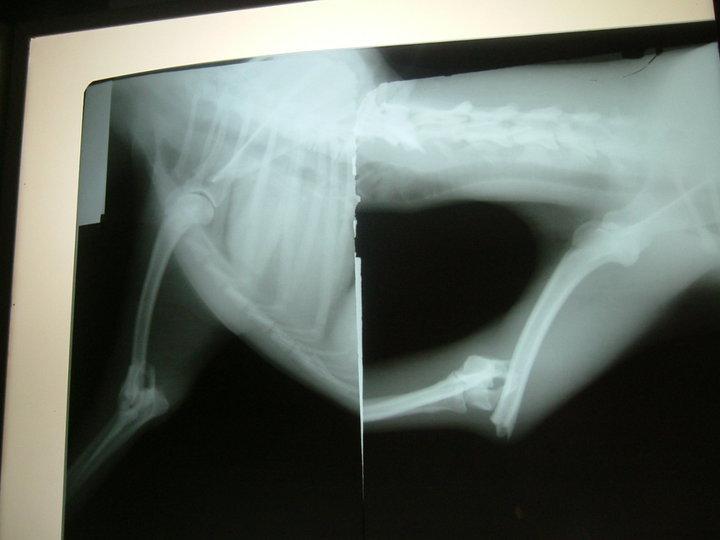

NOVEDADES. COPIO:Ya hemos llevado al pobre Agustin al veterinario y el diagnostico no es demasiado bueno. Tiene una importante rotura que solo puede ser tratada en quirofano. El presupuesto por esta zona es desorbitado y nos dan de plazo solo unos dias para que el problema no se haga mayor. No tenemos dinero para costear dicha operacion, ni siquiera tenemos sitio para tenerlo en unas condiciones dignas; necestamos que alguna protectora o asociacion con mas recursos nos ayude. Difunde por favor Agustin se merece un final feliz tan solo tiene un añito y ya sabe bien lo que es sufrir.